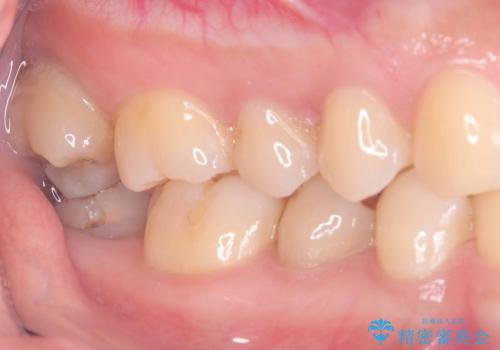

- 税込176,000円(オールセラミッククラウン121,000円+仮歯11,000円+VPT44,000円)費用は治療当時の料金となります

虫歯が神経まで達していましたが、術前の検査でVPTの適応と診断をしていたので、ラバーダムシートを装着しVPTを行いました。

経過も良好で、痛みも無く神経を残すことが出来ました。